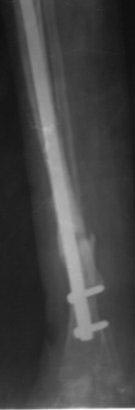

было произведена после рассверливания канала БИОС плечевым стержнем,но

стержень пошел по мед.стенке дистального отломка поэтому остался

некоторый вальгус(операция без ЭОП) ребенок через неделю начал

самостоятельно ходить, клинически деформации нет, все обрадовались,

выписали, повторно приехали только ч-з 1,5 года вот с такой деформацией,

но ребенок ходит в школу, бегает, незначительно хромает, родители

требуют исправить деформацию.

Пока в голове один план: удалить стержень, закрытая остеоклазия, аппарат

Илизарова из двух колец постепенная коррекция деформации, рассверливание

к/м канала, БИОС плечевым стержнем (чуть длиннее), дистально по

латеральному кортексу с использованием поллерных винтов и спиц.